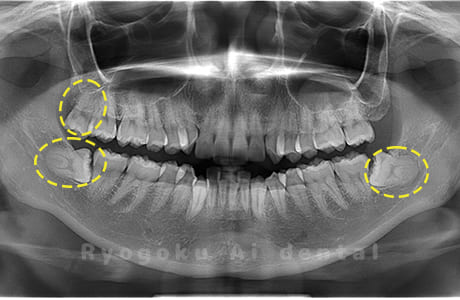

Case04

-

- 原因

- 上顎の親知らず、下顎の水平埋伏の親知らず

- 治療内容

- 上顎の親知らず、下顎の水平埋伏の親知らずを抜歯したケースです。

<リスク・副作用>

手術後は痛み、腫れ、痺れなどの副作用が生じる場合があります。